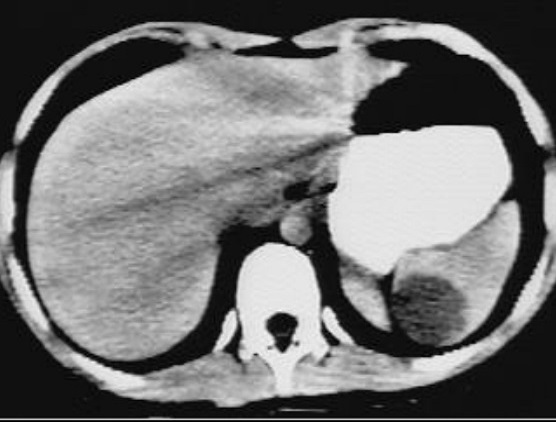

Image

radiologique TDM une rate surnuméraire à petite

taille situe au bord posterieure de la rate ( fléche

raouge ) . Aspect radiologique est une rate petite

homogène a bord nette , lisse , isodensité

retrosplenique |